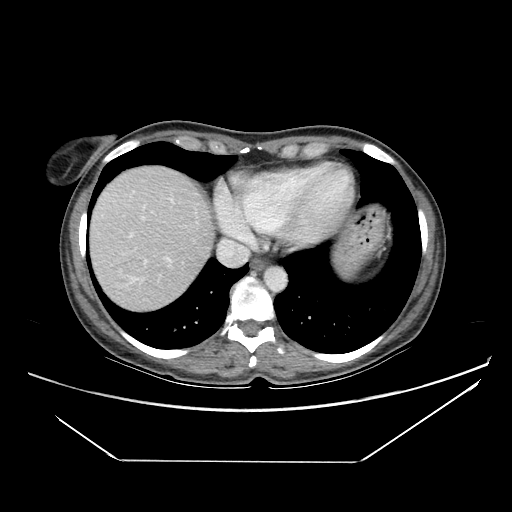

Generated VENOUS CT scan (A→B translation)

No window - Raw intensity values

Lung window (WL -600, WW 1500 β†’ Low βˆ’1350, High +150)

Mediastinum window (WL 40, WW 400 β†’ Low βˆ’160, High +240)